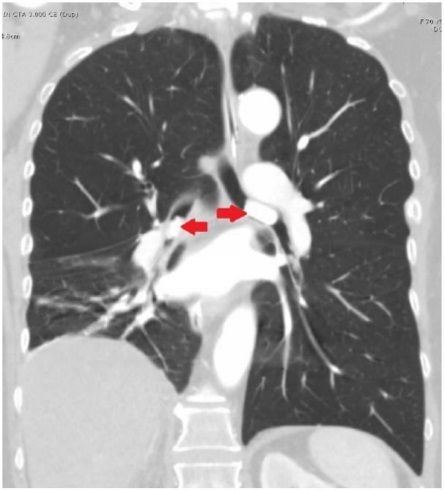

Пациентка обратилась с жалобами на прогрессирующую одышку и кашель в течение месяца. Рентгенография органов грудной клетки показала изменения в правом легком с небольшим количеством жидкости в правой плевральной полости. Но при компьютерной томографии грудной клетки инфильтрации или других изменений легочной ткани не обнаружено. Пациентке назначена эмпирическая антибактериальная терапия. При исследовании мокроты выявлен рост непатогенной флоры. Состояние пациентки продолжало ухудшаться, что потребовало интубации трахеи и искусственной вентиляции легких. При повторной КТ грудной клетки выявлены гиперденсные образования в просвете левого главного (размер 2,2 см) и промежуточного бронхов (размер 1,5 см), обтурирующие их (рис. 1, 2).

Рисунок 1 [1].